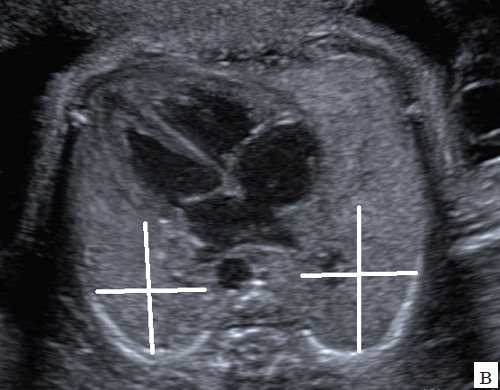

В рамках настоящего исследования мы использовали более традиционные методы оценки легких. Еще в середине 90-х гг. ХХ века была предложена методика пренатального прогнозирования сердечнолегочных осложнений при наличии диафрагмальной грыжи по степени компрессии контралатерального, т.е. условно здорового, легкого. Наиболее популярным критерием оценки постнатального прогноза при диафрагмальной грыже с тех пор стал LHR (lung-head ratio, легочноголовное отношение или ЛГО). Первоначально правое (условно здоровое) легкое при левосторонней диафрагмальной грыже измеряли в срок до 25 нед путем умножения максимальных диаметров, и полученный показатель соотносили с окружностью головы, измеренной при сканировании в стандартной аксиальной плоскости для оценки бипариетального размера (четкая визуализация М-эхо и задних рогов боковых желудочков, расположение полости прозрачной перегородки на расстоянии 1/3 от лобной кости) [4].

В течение последующих лет были проведены многочисленные исследования, направленные на изучение возможностей предложенного метода не только во II, но и в III триместре беременности. Результаты, полученные многими исследователями, существенно отличаются в связи с разными сроками обследования, небольшим количеством пациентов в нескольких сериях исследований, с затруднениями при оценке легкого при правосторонней диафрагмальной грыже и при перемещении в грудную полость печени, что вызывает более сильную компрессию. Несмотря на определенные расхождения в результатах, во многих работах было установлено, что при ЛГО≤1,5 прогноз для новорожденного можно расценить как неблагоприятный или крайне сомнительный, тогда как показатель >2 свидетельствует о хорошем постнатальном прогнозе 6.

- Измерение должно проводиться на уровне четырехкамерного среза сердца.

- Условно здоровое легкое должно располагаться ближе к датчику, чем легкое со стороны грыжи.

- Датчик следует располагать так, чтобы ультразвуковой сигнал шел параллельно ребрам по межреберному пространству во избежание тени, падающей на легкое.

- По получению оптимального среза для измерения (хорошо видны все опознавательные точки) изображение должно быть зафиксировано и затем увеличено так, чтобы аксиальный план занимал весь экран.

- Контралатеральное легкое можно измерить одним из трех способов, перечисленных выше, и затем полученный результат разделить на значение окружности головы для расчета ЛГО. Предпочтение следует отдавать методу трассировки, как наиболее воспроизводимому, особенно в условиях плохой визуализации легкого при диафрагмальной грыже. Необходимо следить за тем, чтобы миокард не входил в измеряемую часть изображения.

- После получения ЛГО следует разделить его на значение ЛГО, соответствующее средним нормативным значениям для срока, при котором проводится исследование.

- Минимальное количество измерений легких для достижения стабильного результата должно быть не менее 70. Желательно, чтобы врач, проводящий измерения, прошел курс специальной подготовки у врача-эксперта.

В нашем исследовании во всех случаях проводилась оценка контралатерального легкого по описанной выше методике двух перпендикуляров с использованием 2D режима и сохранялось двухмерное изображение с положением калиперов, фиксирующих размеры легкого. При получении значений ЛГО≤1,5 постнатальный прогноз расценивался как крайне сомнительный. В момент исследования объемная информация фиксировалась в архиве ультразвукового аппарата, но не обрабатывалась.